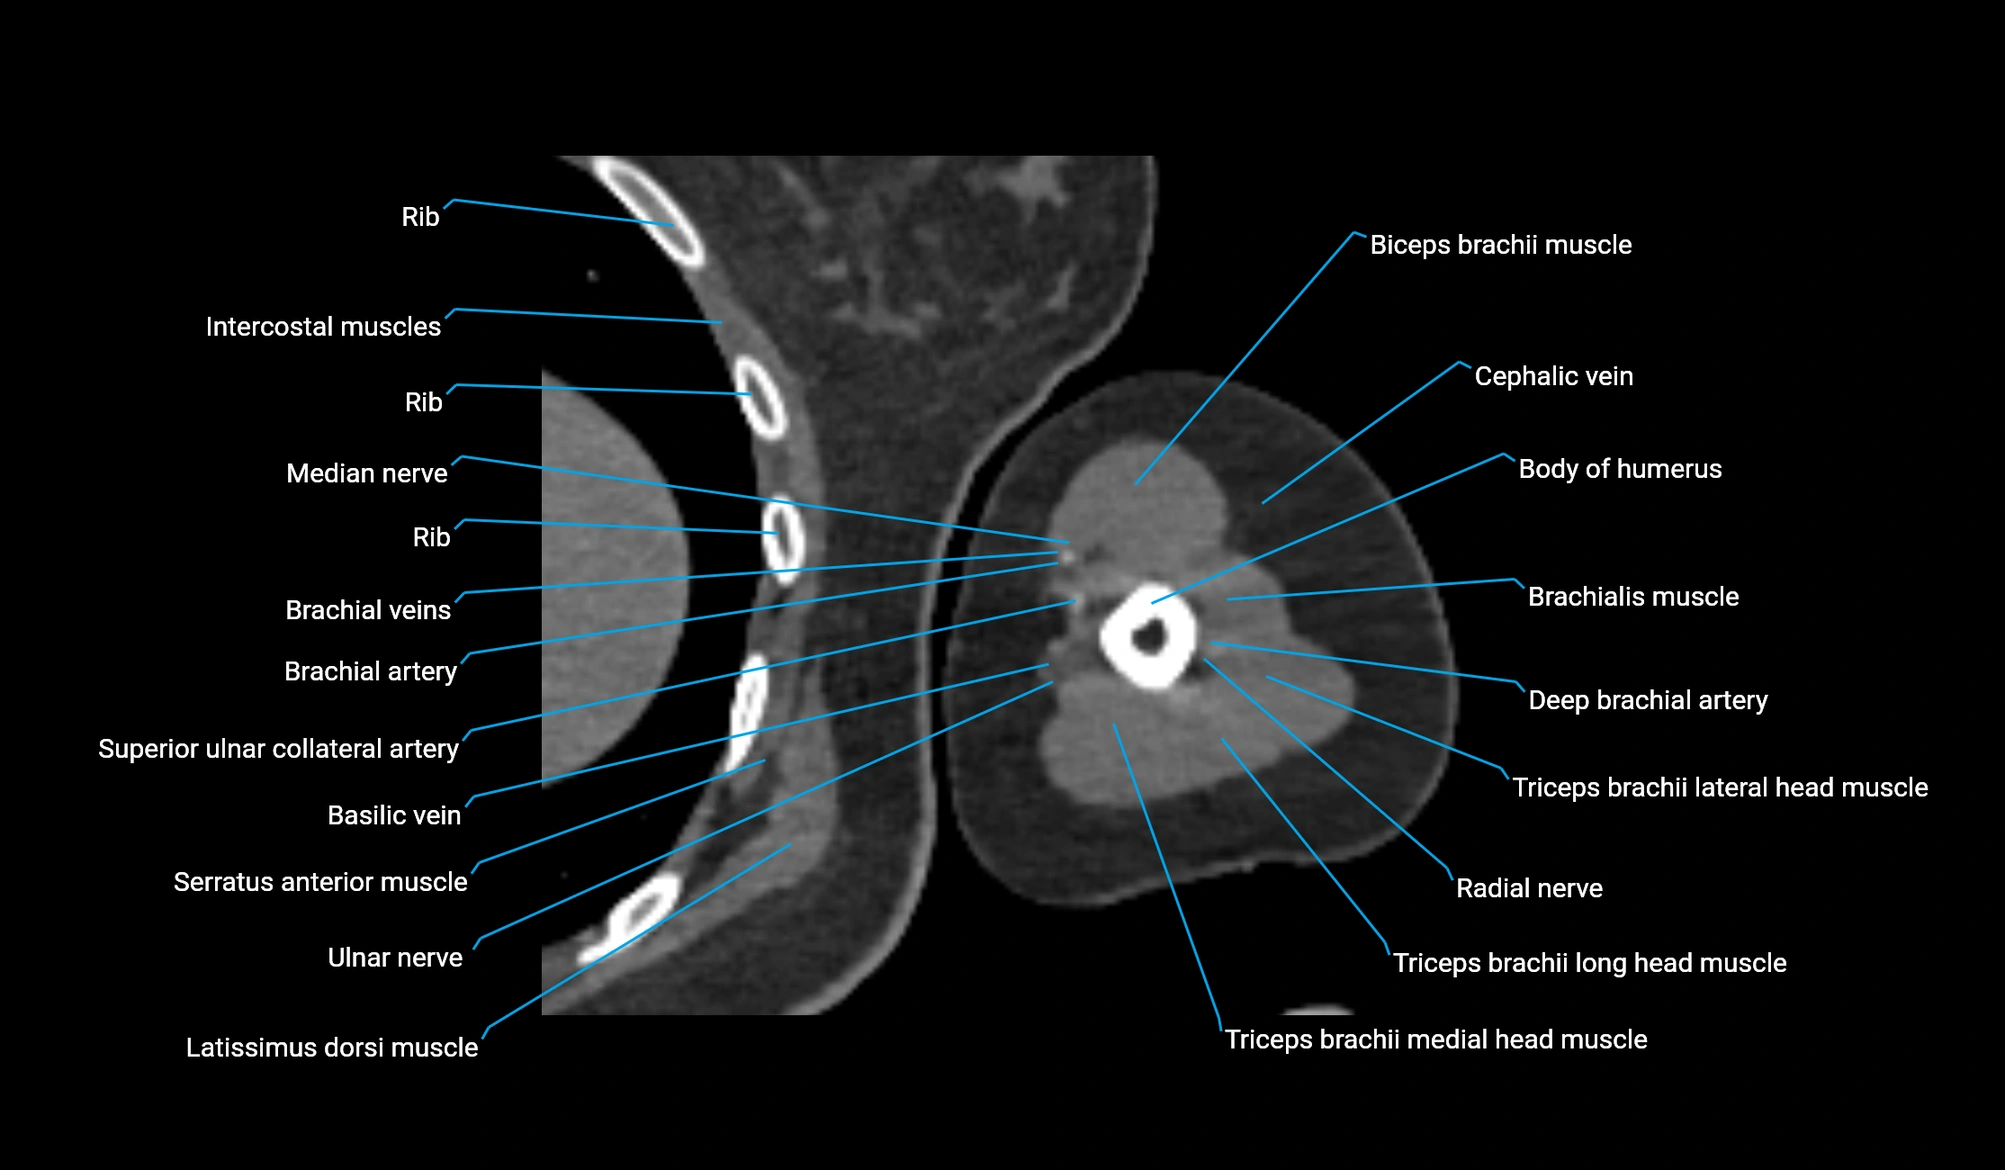

CT image